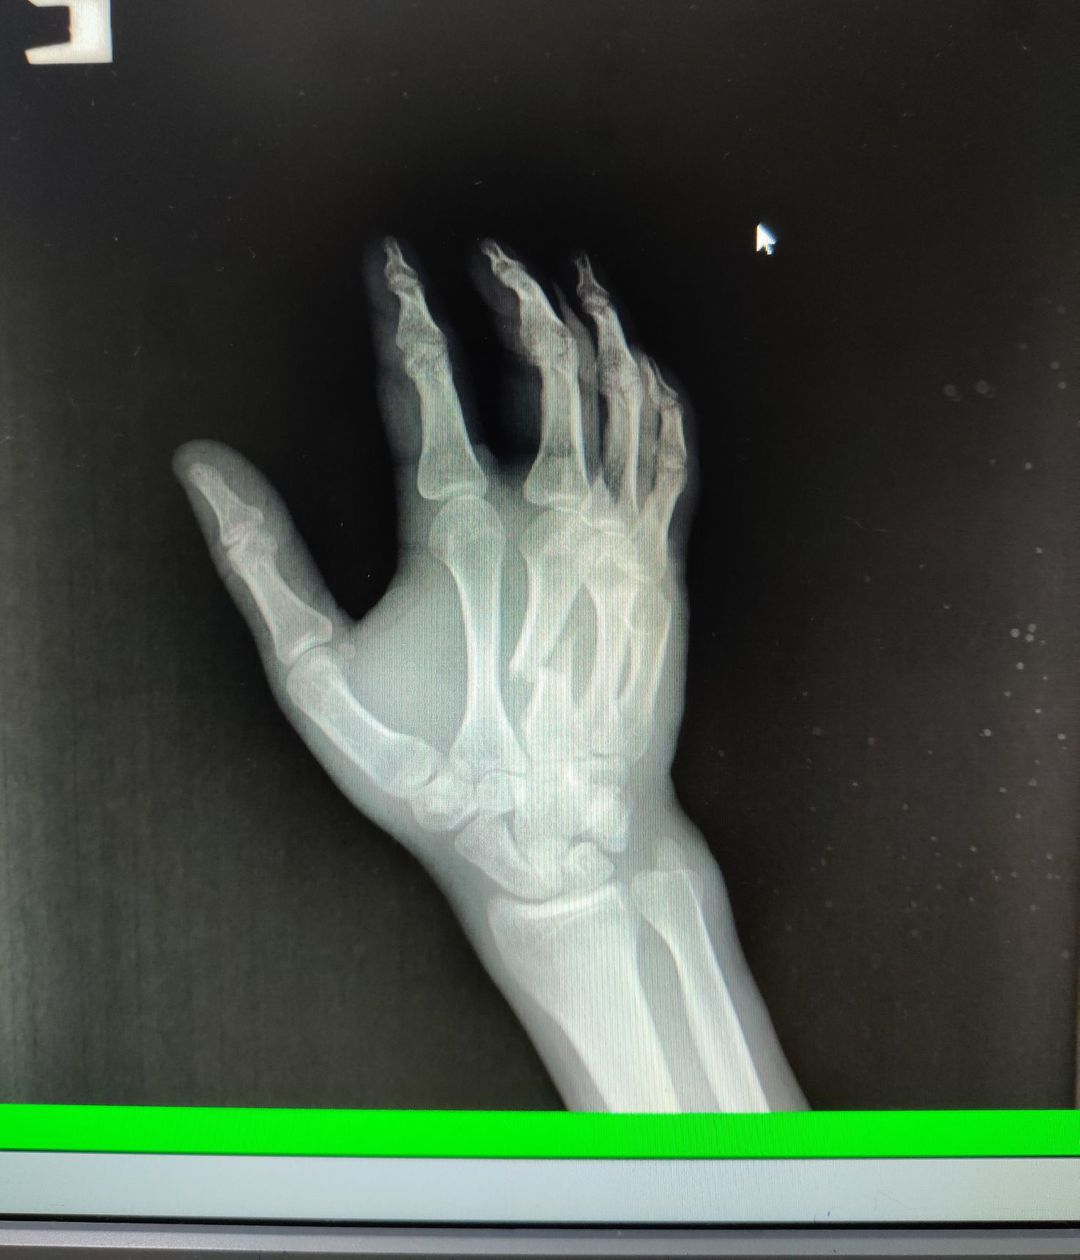

Patient was cooking beef, poked his arm with a knife

Xray

Fracture